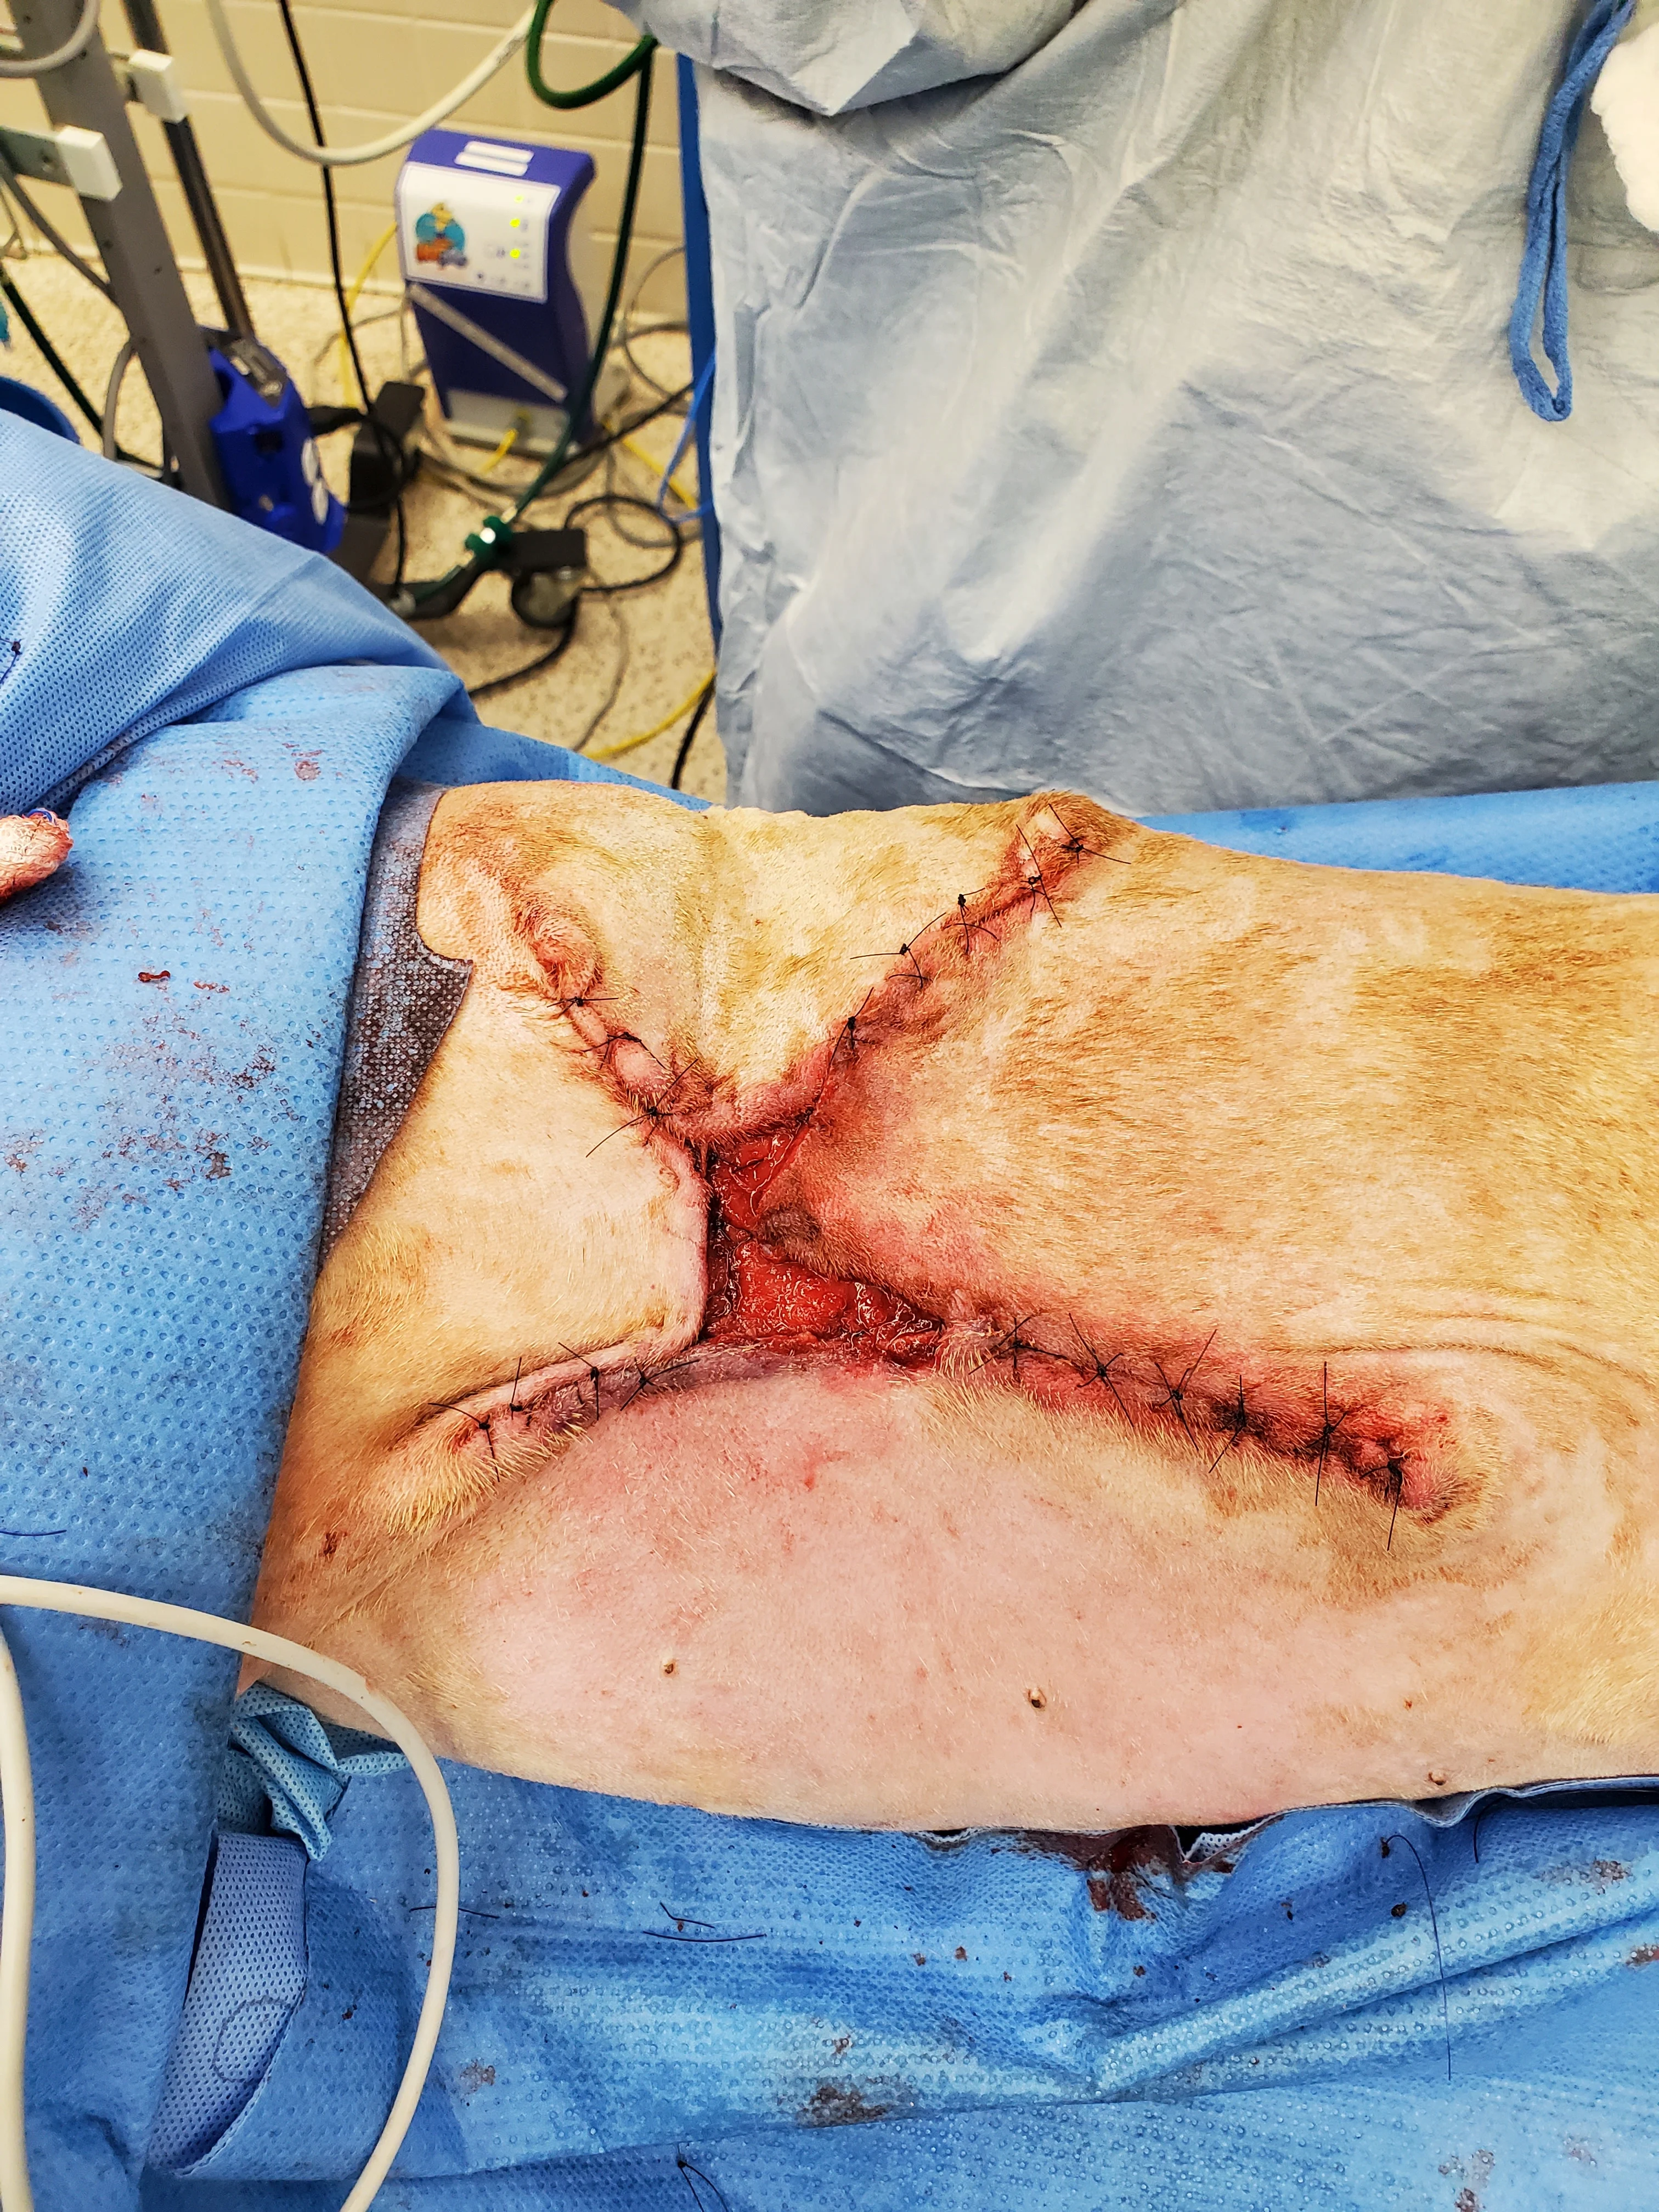

Figure 7 Seven days after presentation, the wound started filling with granulation tissue, and there was no further appearance of necrotic tissue (A). Surgery for partial wound closure was performed, with the skin elevated and undermined around the wound bed and advanced toward the center (B). Free edges were tacked down to the underlying wound bed. Walking sutures and subcutaneous tacking sutures were not used to avoid damaging the remaining blood supply.17 The central open wound was covered with a silver-impregnated, soft silicone foam dressing and a soft padded bandage.

Surgical closure of large, traumatic wounds should be delayed until the surrounding skin appears normal and contusions, edema, and infection have resolved.17 Once the wound bed is healthy, local and regional skin conditions should be considered to select a closure technique. In this patient, the health of nearby vascular pedicles was a concern because of the original skin avulsion and degloving; therefore, immediate complete closure and axial pattern and advancement flaps were not used. Instead, local tissues were undermined to release their attachments and maximize their elastic potential without overstretching the skin.17 Large wounds may close with less tension if they are envisioned as a triangle or rectangle and sutured from the corners inward in a Y- or X-shape.18